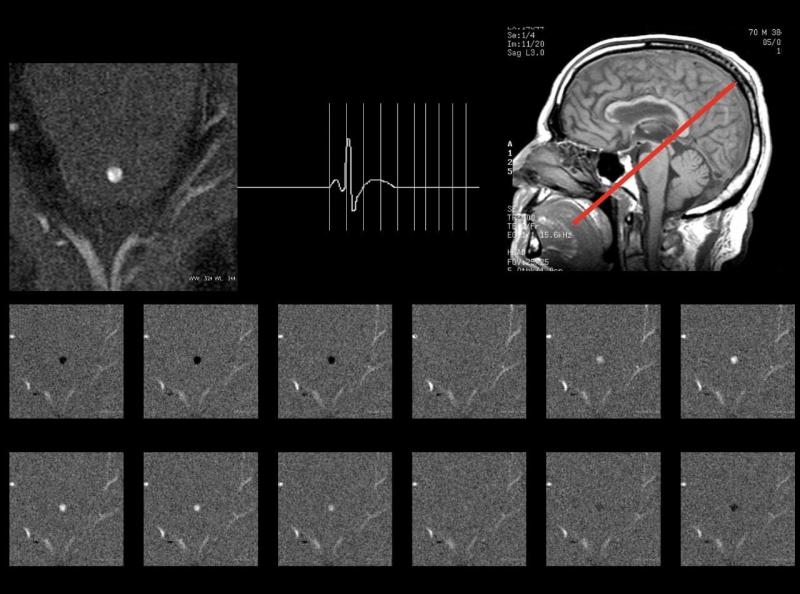

| Cine Phase-Contrast (PC-MRI) | Estudo dinâmico do fluxo do LCR com codificação de velocidade. | VENC ajustado entre 5 e 20 cm/s, plano sagital no aqueduto. |

- Plano de corte: Sagital mediano como referência principal para planejamento.

- Área de interesse: Todo o trajeto do LCR, incluindo ventrículos, aqueduto cerebral e espaço subaracnóideo.